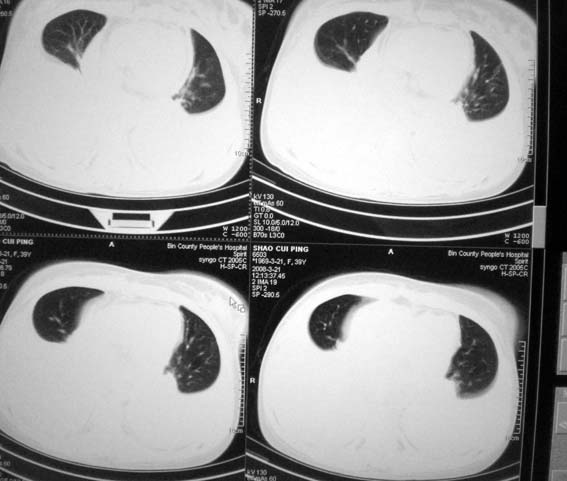

以下是引用zsl6918在2008-3-21 21:41:00的发言:[br]胸腔积液,心包积液,明确性质有难度。常规思路考虑结核性,建议抽液化验明确。

以下是引用卜一在2008-3-22 1:48:00的发言:[br][br] [br] 大量胸腔积液伴肺组织膨胀不全+心包积液。建议行纤支镜! [br] [br]

以下是引用随光逐影在2008-3-21 23:13:00的发言:[br]1)右肺中叶及左肺上叶舌段感染性病变。2)右肺中叶周围型肺癌待排。3)双侧胸腔积液并双下肺部分肺组织膨胀不全。4)心包积液。

以下是引用拾荒者在2008-3-22 21:21:00的发言:[br]胸腔积液、心包积液,双下肺膨胀不全,建议穿刺细胞学检查或抽液后进一步ct检查。